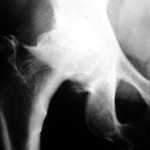

artrosi foto